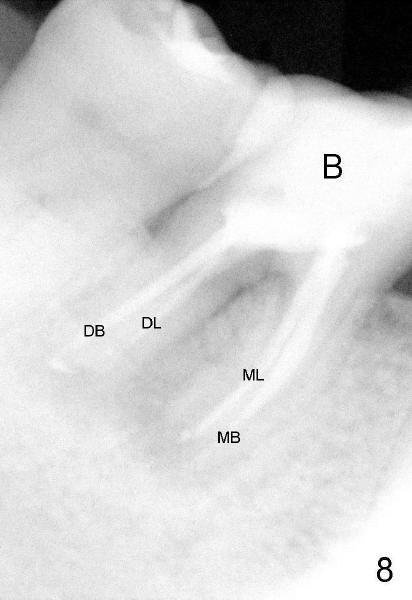

To further improve visibility, the arm of rubber dam clamp is changed from distal to mesial aspect of #30 (compare R in Fig.6 and 7). DL orifice is finally found, close to DB one. The DL canal is obliterated. It is debrided until #20 hand file short of WL. Fig.7 shows the chamber after RCT with gutta percha. * indicates thin pulpal floor. Fig.8 and 9 are taken after build-up (B). It appears that distal canals are divergent apically and that there are most likely two distal roots.